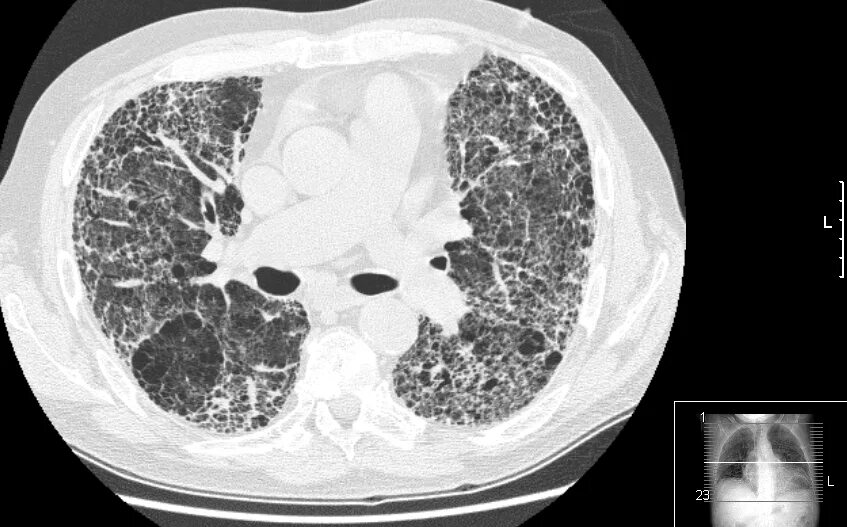

Фиброз кт